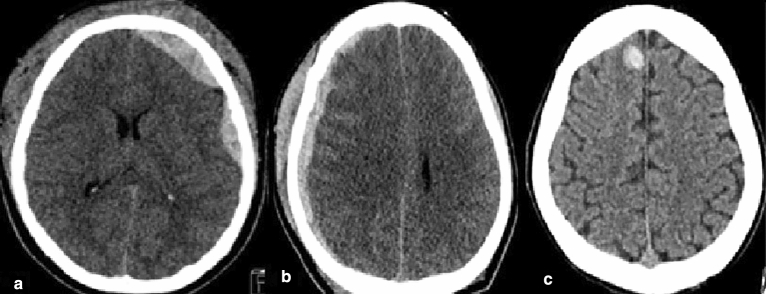

Figure 3.

Identification and Localization of ICH: (a) EDH at left cerebral convexity, (b) SDH at right cerebral convexity, (c) IPH at right cerebral hemisphere.